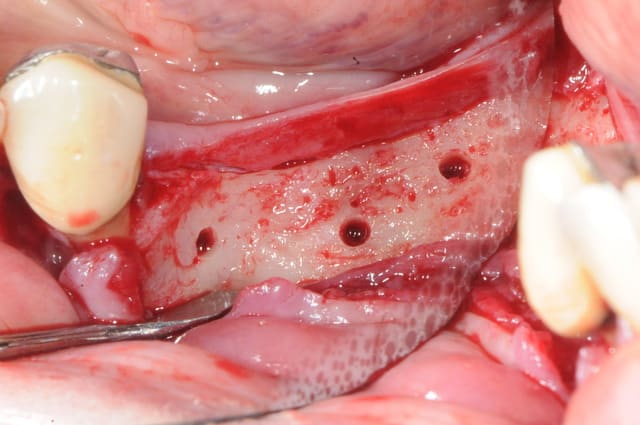

voici peut être une autre solution qui te satisfera d'avantage car beaucoup plus simple à mettre en œuvre.

c'est une simple ROG avec des vis pour maintenir l'espace sous la membrane.